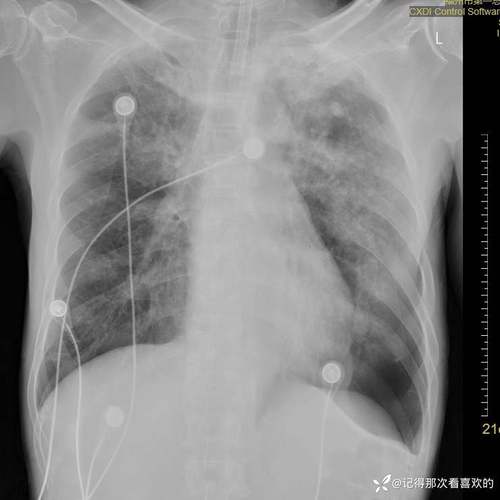

(图片来源网络,侵删)